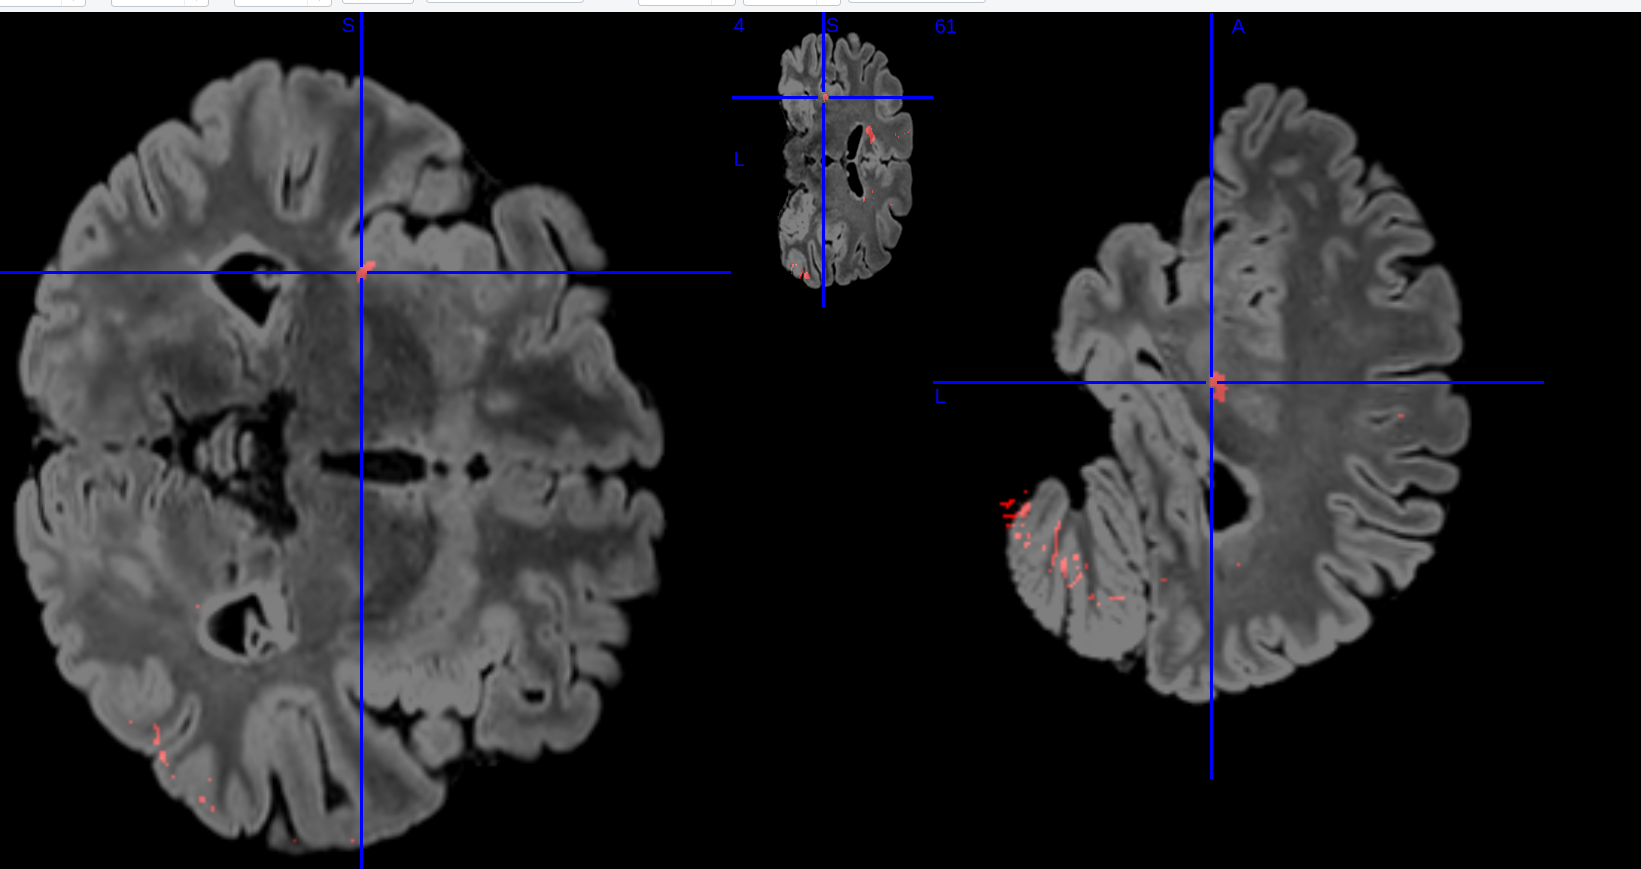

One of the most widely used deep learning architectures is the U-Net [3] introduced in 2015. Its variants, such as the V-Net [4], are also gaining popularity. Notable performance in MS lesion segmentation was achieved by the method introduced by [5] in 2017 reporting a dice score of 87.2. Therefore, the focus shifted to achieving more detailed disease monitoring using deep learning. The next step which is longitudinal MS segmentation, which uses scans from two or more time points to identify newly emerging lesions. These new lesions are crucial markers of disease progression and inform treatment planning [6]. This is illustrated in figure 1 where the follow-up scan shows the new lesion delineated in red.

Figure 1: Baseline and Follow-up scans of the MSSEG dataset

We made use of the Multiple Sclerosis New Lesion Segmentation challenge 2 (MSSEG’2)111https://portal.fli-iam.irisa.fr/msseg-2/ dataset which is a follow-up to the MSSEG 2016 dataset which wasn’t longitudinal[22]. It is a dataset focusing on newly appearing MS lesions with data from two time-steps being provided and contains 365 slices per Magnetic Resonance Imaging(MRI) scan.

The dataset comprises the MRI data of 100 MS patients. The patients have two scans as demonstrated in figure 1 - the baseline and the follow-up scan - with all scans being of the FLAIR modality. The follow-up scans are taken 1-3 years after the baseline. The scans are taken from 15 different scanners with data from the 3 GE scanners being withheld in order to assess generalisability. The data from 40 patients is available to the public with the rest being kept under wraps as an unseen test set for the challenge itself. Ground-truth was provided for 4 experts as well as a consensus new lesions mask. We only used the latter.

Figure 6: Qualitative comparison of segmentation outputs

4.1 Qualitative

Figure 6 shows a qualitative comparison and we compare HyTver’s output with Dice and Cross Entropy loss which are the most commonly used loss functions. We use the sample that got the worst performance output consistently during training. This low score is due to the asymmetrical shape of the lesion which can be difficult to segment. We can see that HyTver has less false positives compared to Dice and Combo loss although it slightly underestimates the size of the leftmost lesion. Dice and Cross Entropy are slightly better at estimating the size of the leftmost lesion, they also come with a much higher number of false positives. Thus HyTver proves to have good segmentation performance while ensuring low false positives and false negatives.